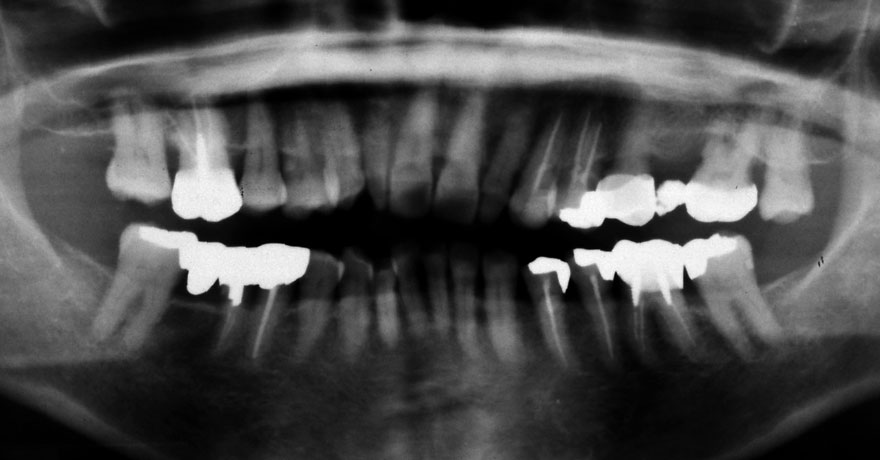

初診時 50歳 女性

河田歯科医院

30年後 80歳